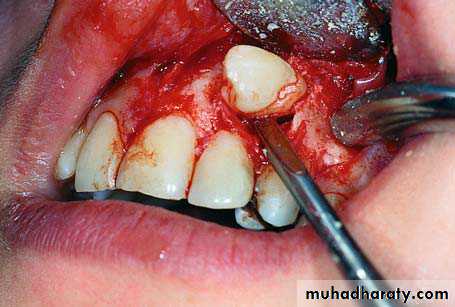

Extraction by the buccal approach

Three sided flap is designed so that complete interdental papilla is left at each corner .after the flap has been raised a bony bulge may be visible or palpable indicating the site of the impacted tooth .Mosul university- College of dentistry-oral & maxillofacial surgery department

Sufficient overlying bone is removed to expose the crown of the impacted tooth .if root configuration prevent simple elevation the root should be exposed over a good part of its length before further force is applied .if delivery of the canine still can not be effected , the tooth must be divided at its neck and the 2 segments removed separately .